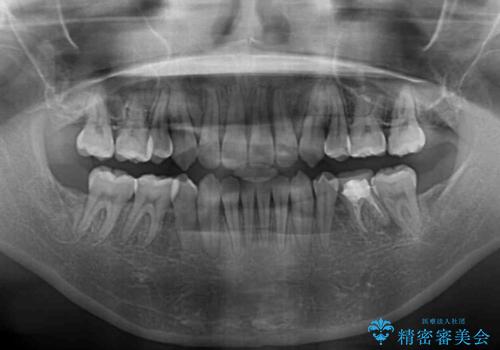

上顎左右第一小臼歯2本、下顎左右第二小臼歯2本を抜歯し、ワイヤー装置にて口元を引っ込めるよう矯正治療を行うこととしました。

上下の前歯に隙間が空くほど上顎前歯が前に飛び出していましたが、抜歯矯正により上下前歯がぴったりと付くほど口元を引っ込めることができました。